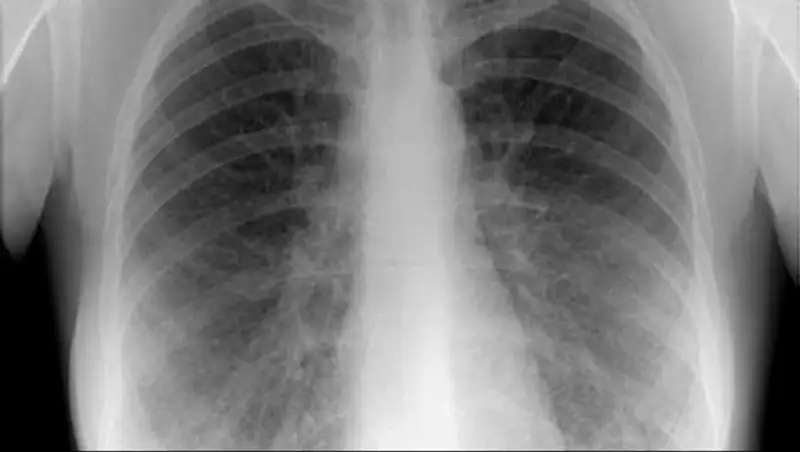

Сегодня с самого утра в нашу редакцию звонят взволнованные родители столичных школьников, сообщает Седьмой канал. Люди напуганы слухами о, якобы, участившихся случаях заболевания туберкулеза среди детей. Говорят, в учебных заведениях массово вакцинируют учеников, и активно информируют о последствиях этого недуга. Стало известно и о новом факте заболевания третьеклассника в Астане.

Медсестра этой столичной школы проверяет результаты пробы манту. Несколько дней назад детям ввели подкожно туберкулин. Говорит, что процедура плановая. Только в последнее время все больше положительных результатов. Это значит, что дети находятся в группе риска. Под особым контролем ученики 4 класса. Именно там произошел случай заболевания туберкулезом. Школьник сейчас получает лечение.

Еще один случай заболевания туберкулезом зафиксирован уже в 2015 году у третьеклассника восьмой школы Астаны. Об этом сообщают в столичном тубдиспансере. По спискам, которые имеются здесь, на лечении сейчас находятся 22 ребенка. Из них 13 - ученики столичных школ. По анализу специалистов, почти все поступившие дети переехали в Астану из других регионов страны.

По словам врачей, туберкулез - болезнь коварная, протекающая, как правило, без клинических симптомов. Медики призывают родителей еще в роддоме вакцинировать своих детей и не отказываться от пробы манту. Говорят, недуг может напасть на любого, независимо от социального статуса.